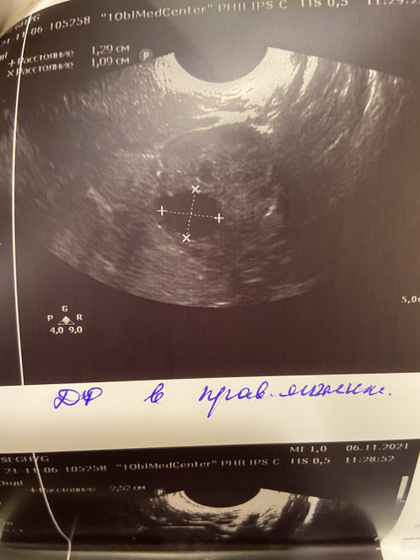

Сегодня была на узи, уже доминантный фолликул есть справа, овуляция дня через 3-4 примерно, начала делать тесты, НО, эндометрий снова тонковат(((( я прям очень переживаю за него, может из за его толщины не прикрепляется эмбрион? До последнего выкидыша никогда проблем не было с эндометрием! Верю что подрастёт ещё за несколько дней! Пожелайте удачи! ?